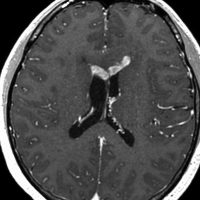

ガドリニウム増強では,前頭葉腫瘍というより,側脳室壁にベトベトくっついているような腫瘍です。germinoma特有のsubependymal infiltration像を示します。

左はICE化学療法 (IFO/CDDP/VP-16)前,右は1コース終了後です。腫瘍は顕著に縮小してgerminomaとして普通の化学療法反応性を示します。また,松果体と下垂体には腫瘍はありません。